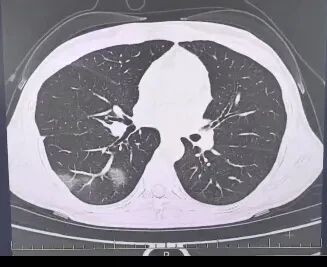

呼吸内科医师了解到她口服速福达抗流感病毒后仍反复发热,并咳出黄色浓痰,立即安排了相关检查。结果情况反而进一步加重:好几叶肺叶都出现了“白肺”现象,指间血氧饱和度只有88%,血心肌酶谱、肌钙蛋白的指标、肝功能的指标也出现了明显的异常。

图源:杭州市第三人民医院微信公众号

家长见状,再次带小婷到该院就诊,检查结果让他们后悔不已——肺部CT显示,小婷的右肺出现大片实变,也就是俗称的“白肺”。